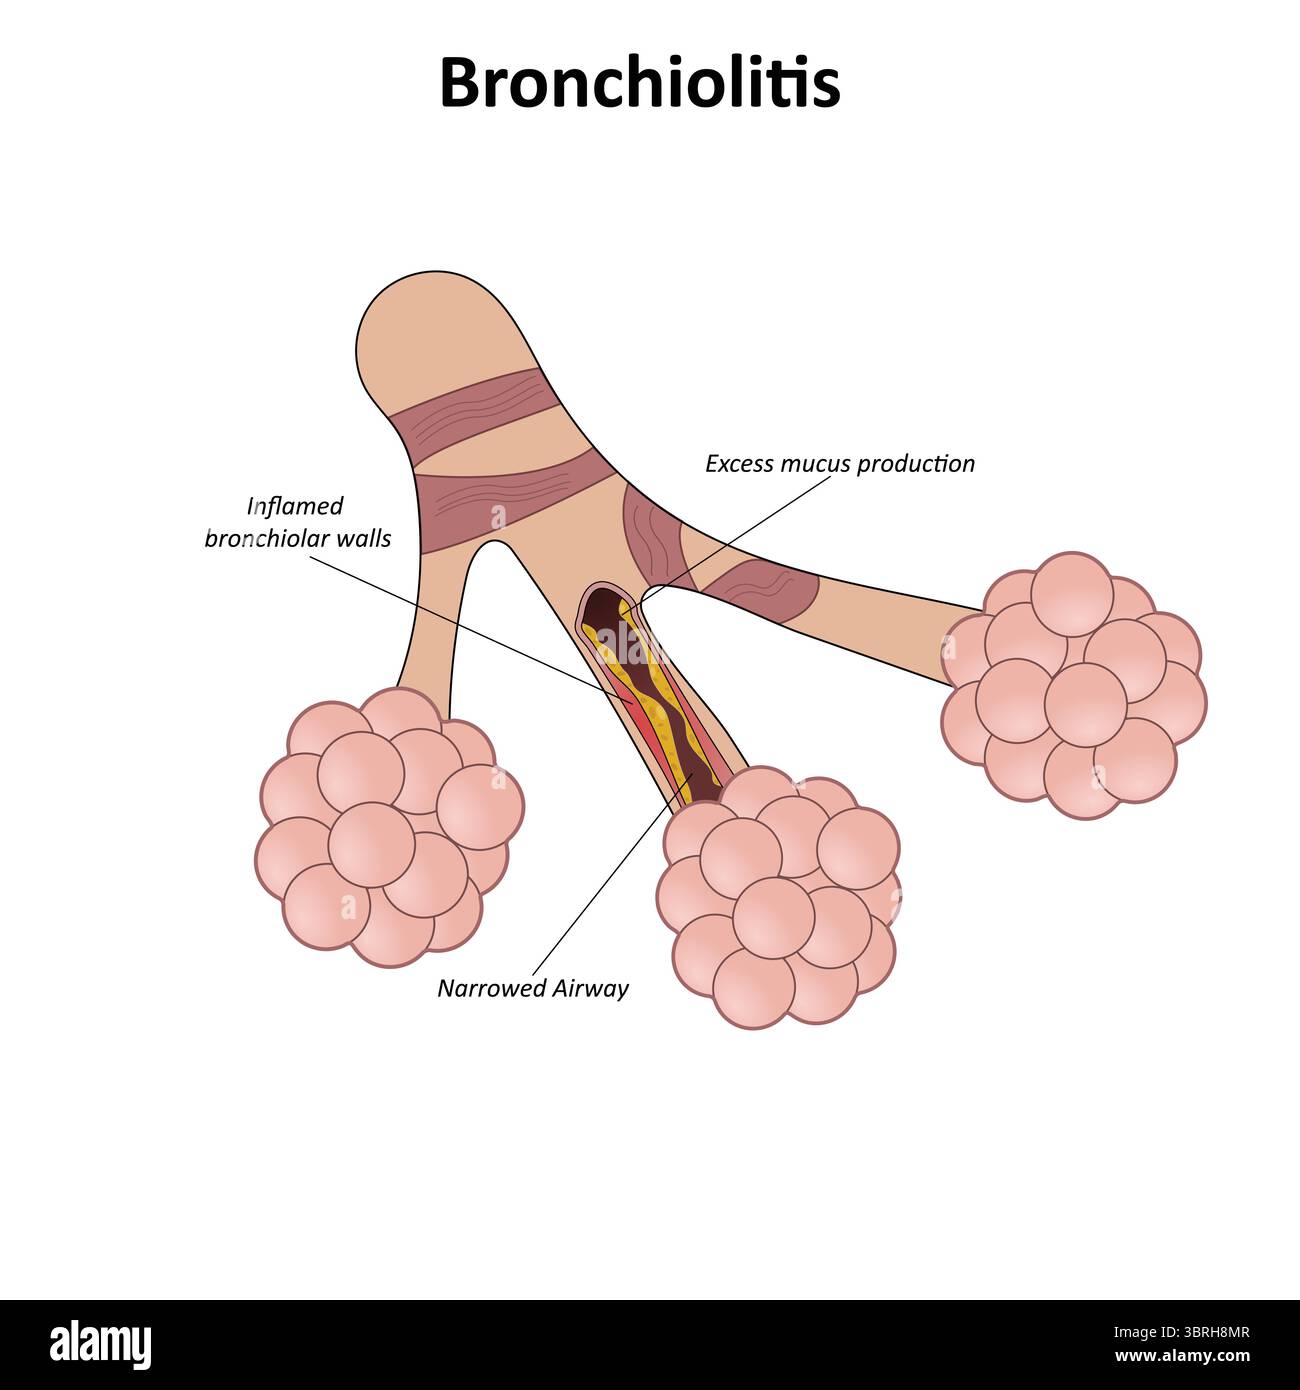

Bronchiolitis vector illustration Stock Vectorhttps://www.alamy.com/image-license-details/?v=1https://www.alamy.com/bronchiolitis-vector-illustration-image685721432.html

Bronchiolitis vector illustration Stock Vectorhttps://www.alamy.com/image-license-details/?v=1https://www.alamy.com/bronchiolitis-vector-illustration-image685721432.htmlRF3BRH8K4–Bronchiolitis vector illustration

Bronchiolitis vector illustration Stock Vectorhttps://www.alamy.com/image-license-details/?v=1https://www.alamy.com/bronchiolitis-vector-illustration-image685721479.html

Bronchiolitis vector illustration Stock Vectorhttps://www.alamy.com/image-license-details/?v=1https://www.alamy.com/bronchiolitis-vector-illustration-image685721479.htmlRF3BRH8MR–Bronchiolitis vector illustration